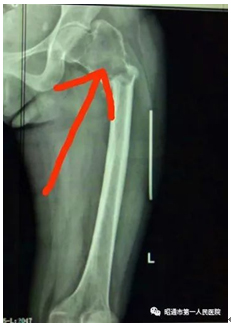

相关检查后县医院考虑股骨近端骨肿瘤并股骨病理性骨折,并开始给予相应对症治疗。但是天不遂人愿,几经治疗均无好转。县医院医生只得摇摇头,无奈地建议前往省级医院进一步治疗,也许会有转机。作为建档立卡户,家中已经一贫如洗,加之之前的医疗、人力支出,如何还能承受往返省城的费用,况且身处异地全无照应,这一笔开支又如何得来?

(术前影像)

入住我院创伤外科后,值班医生详细询问其状况,安排她进行全面检查,并将病情告知其余医护。在与患者及家属的沟通过程中,值班医师阐明意见,综合检查结果、既往病史等各种考虑,必须进行手术;依照流程须将治疗计划以及手术风险等情况如实告知家属,由家属知晓同意并签字才能开展手术,这也是依法执医的要求。